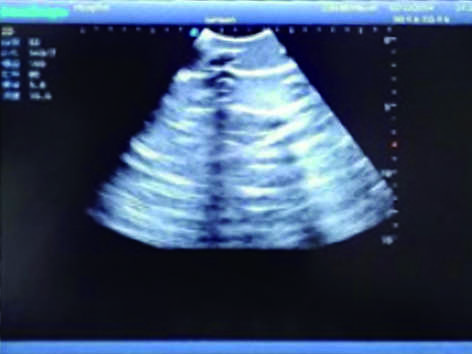

2) Made of high molecular polymer ultrasound material, close to the real skin. It can conduct ultrasound-guided puncture exercises with various clinical models of real ultrasound machines.

3) Showing clear and real images of the tissues and organs (including muscle and connective tissue, air-containing lung tissue, pleural structure)